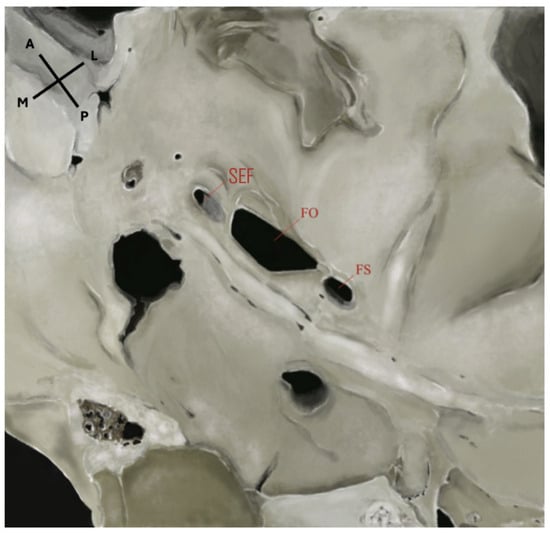

The sphenoidal emissary foramen (SEF)—also known as the foramen Vesalii or foramen venosum—is an inconstant and highly variable foramen situated in the greater sphenoidal wing within the MCF (Figure 1 and Figure 2). It is usually positioned anteromedially to the FO and FS, and posteromedially to the foramen rotundum (FR). Its extracranial aperture opens into the scaphoid fossa, located within the pterygoid process [6,7]. SEF may occur unilaterally or bilaterally and, although rare, may appear duplicated. When it forms a complete canal across the cranial base and remains patent, it becomes clinically significant, as it may transmit a venous channel between the pterygoid venous plexus and the cavernous sinus (CS).

Figure 2.

Extracranial view of the middle cranial fossa showing the foramina of the sphenoid bone. SEF: sphenoidal emissary foramen; FO: foramen ovale; FS: foramen spinosum. An accessory foramen spinosum is also visible extracranially, located medial to the FS. Orientation: A = anterior; P = posterior; L = lateral; M = medial. Source: Image obtained from osteological specimens after essential modification at the Anatomy Laboratories of Andrés Bello University, the University of Santiago de Chile, and Finis Terrae University, Santiago, Chile. All specimens were used exclusively for teaching and research purposes under institutional ethical approval (Resolution S:69-2024-1071).